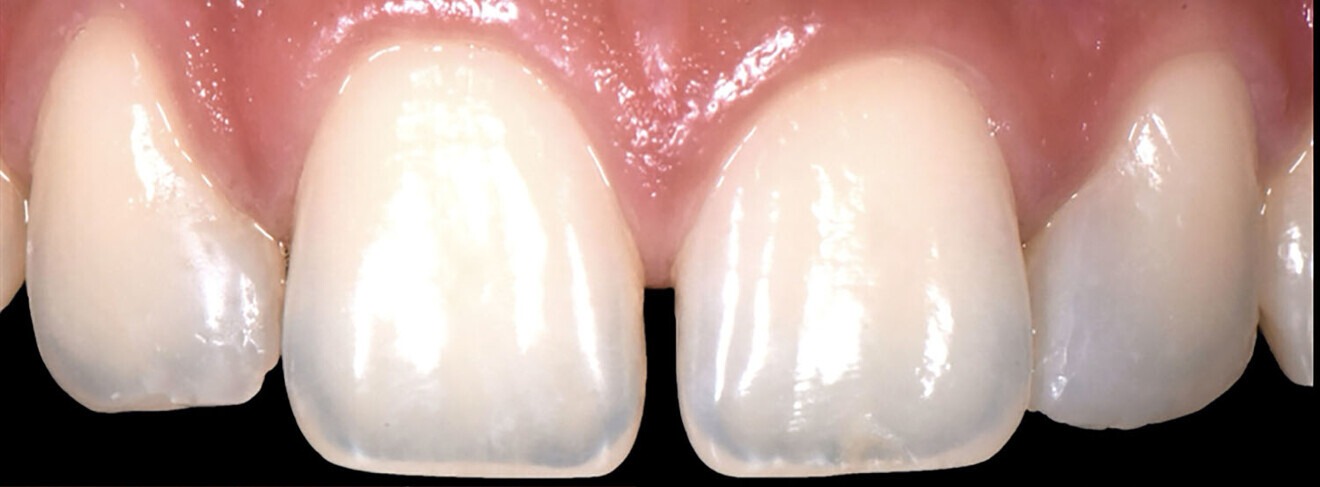

We followed a thorough analysis of the chromatic spectrum, as described by Naorungroj, to accurately and precisely establish the shades to be used in the operative steps (Fig. 2).1 The photographic material was carefully analysed to determine the ideal work planes to gain the information required to achieve the ultimate aesthetic aim of the treatment.

Figs. 2a–d: Choice of shade values.